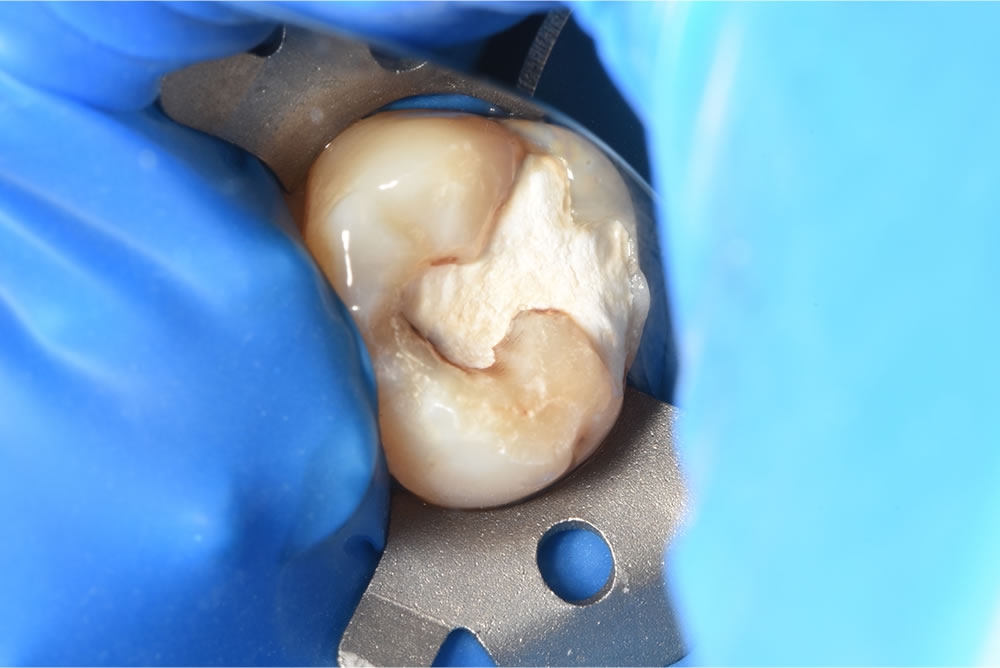

口腔内を拝見すると、左上7番の咬合面にセメント充填がされている状態でした。患者さまにお聞きすると、他院にてとりあえず応急処置を行い、金属での修復を勧められたとのことでした。

う蝕検知液の使用

う蝕検知液を使用します。う蝕の部分だけを染色し、健康な歯質は削らずに治療することが可能となります。う蝕除去を行うと、残存歯質が薄くなっている部位やヒビが入っているところはありませんでした。ダイレクトボンディング治療が可能と判断し、予定通り治療を進めます。